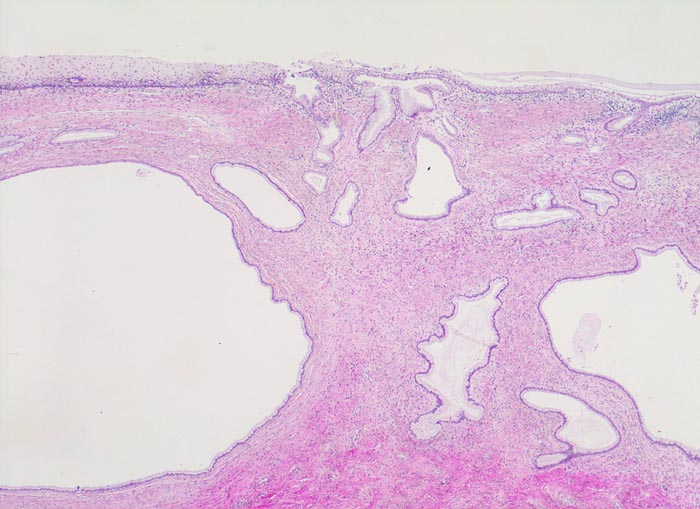

PathoPic – image database / PathoPic ID 4186 - Umwandlungszone mit Zervixdrüsenretentionszysten

Umwandlungszone mit Zervixdrüsenretentionszysten

Umwandlungszone: metaplastisches Plattenepithel bedeckt das endozervikale Drüsenfeld. Die Plattenepithelmetaplasie führt zu Verschlüssen der Drüsenausführgänge. Deshalb ist ein Teil der endozervikalen Drüsen stark dilatiert.